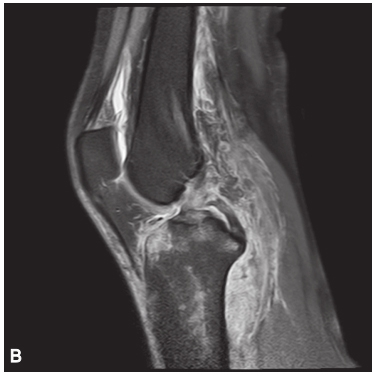

(4)Hoffa 骨折

股骨髁冠状面的骨折称为Hoffa 骨折,Friedrich Busch 在 1869 年首次描述此种类型的骨折,直到 1904 年 Hoffa 详细描述股骨髁外侧髁骨折并命名,随着时间发展,临床上逐渐把股骨内外髁冠状面的骨折都归于 Hoffa 骨折。

Hoffa 骨折属于关节内骨折,常伴髌骨、半月板、交叉韧带、副韧带及胫骨平台的损伤,由于其特殊的解剖结构,此型骨折的发生率极低, 在股骨远端骨折中不足 1%,一般发生在外侧髁。